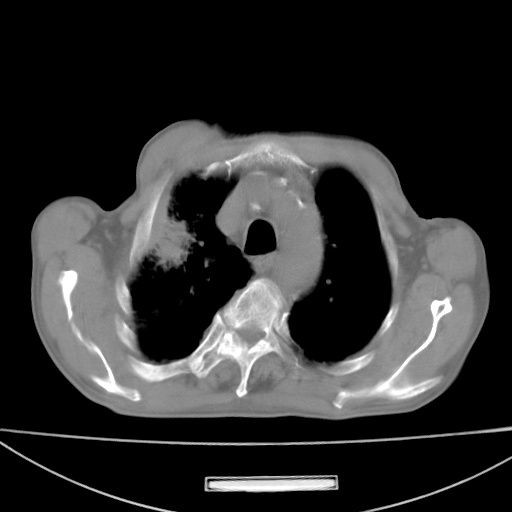

标题: CT13796:请会诊右上费病变!

患者男80岁,反复咳嗽多年,咳喘伴咯血1月

右上肺周围型肺癌伴肺门、纵膈淋巴结转移

考虑为:右肺上叶肺癌伴阻塞性肺炎、右肺门及纵膈淋巴结转移。